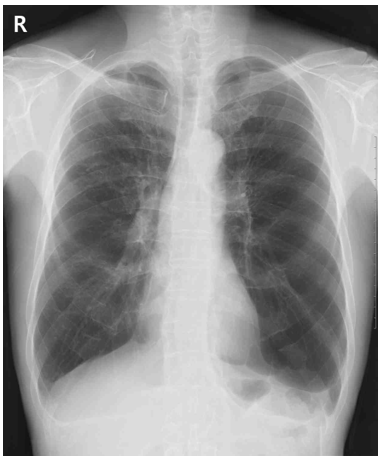

66세 남자가 3일 전부터 숨이 찬다며 병원에 왔다. 수년 전부터 오르막을 오를 때 숨이 찼는데 1주 전 기침이 나고 가래가 늘면서 숨이 더 찬다고 한다. 45갑•년의 흡연자이다. 혈압 124/86 mmHg, 맥박 98회/분, 호흡 22회/분, 체온 36.7°C이다. 양쪽 가슴에서 쌕쌕거림이 들린다. 맥박산소측정 시 산소 포화도는 99%이다. 가슴 X선 사진이다. 치료는?

CXR: Lung hyperinflation

• 청진 시 양쪽 폐에서 쌕쌕거림이 들렸으며, CXR에서 폐의 과팽창이 관찰되었다. 이를 바탕으로 기저 질환으로 COPD를 가지고 있을 가능성이 높다고 판단된다.

• CXR상 폐 과팽창 소견을 판단할 때 평평해진 횡격막의 윤곽과 midclavicular line에서 횡격막 level 위 6개 이상의 anterior rib이 보이는 경우로 생각하고 해석하여도 국시 수준에서는 큰 문제가 없다. 이외 과투명한 폐실질 및 수평화된 갈비뼈 등의 소견을 참조할 수 있다.